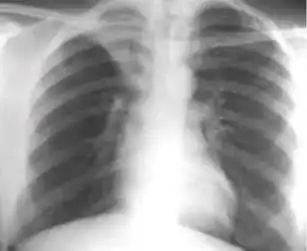

Distinct fibrotic scar and hilar opacity following secondary tuberculosis on chest x-ray

Causes such as bacterial and fungal infections are associated with diffuse abdominal pain, intraperitoneal fluid accumulation, weight loss, fevers, and night sweats. The most common radiographic feature among patients with suspected tuberculous peritonitis was septated compartments of ascitic fluid on ultrasound and abnormal chest X-ray suggestive of previous tuberculosis.[7]